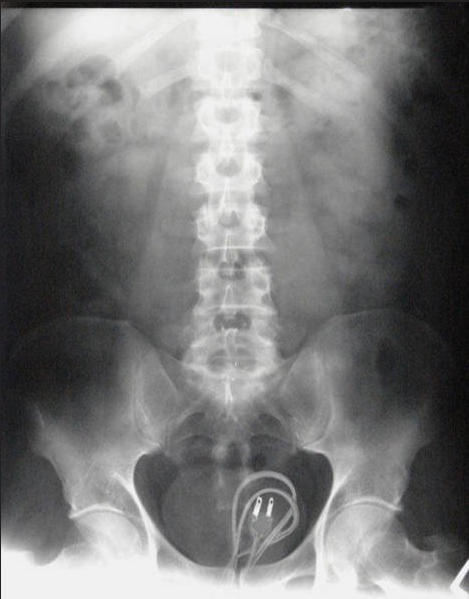

・究極のマナーモード!?